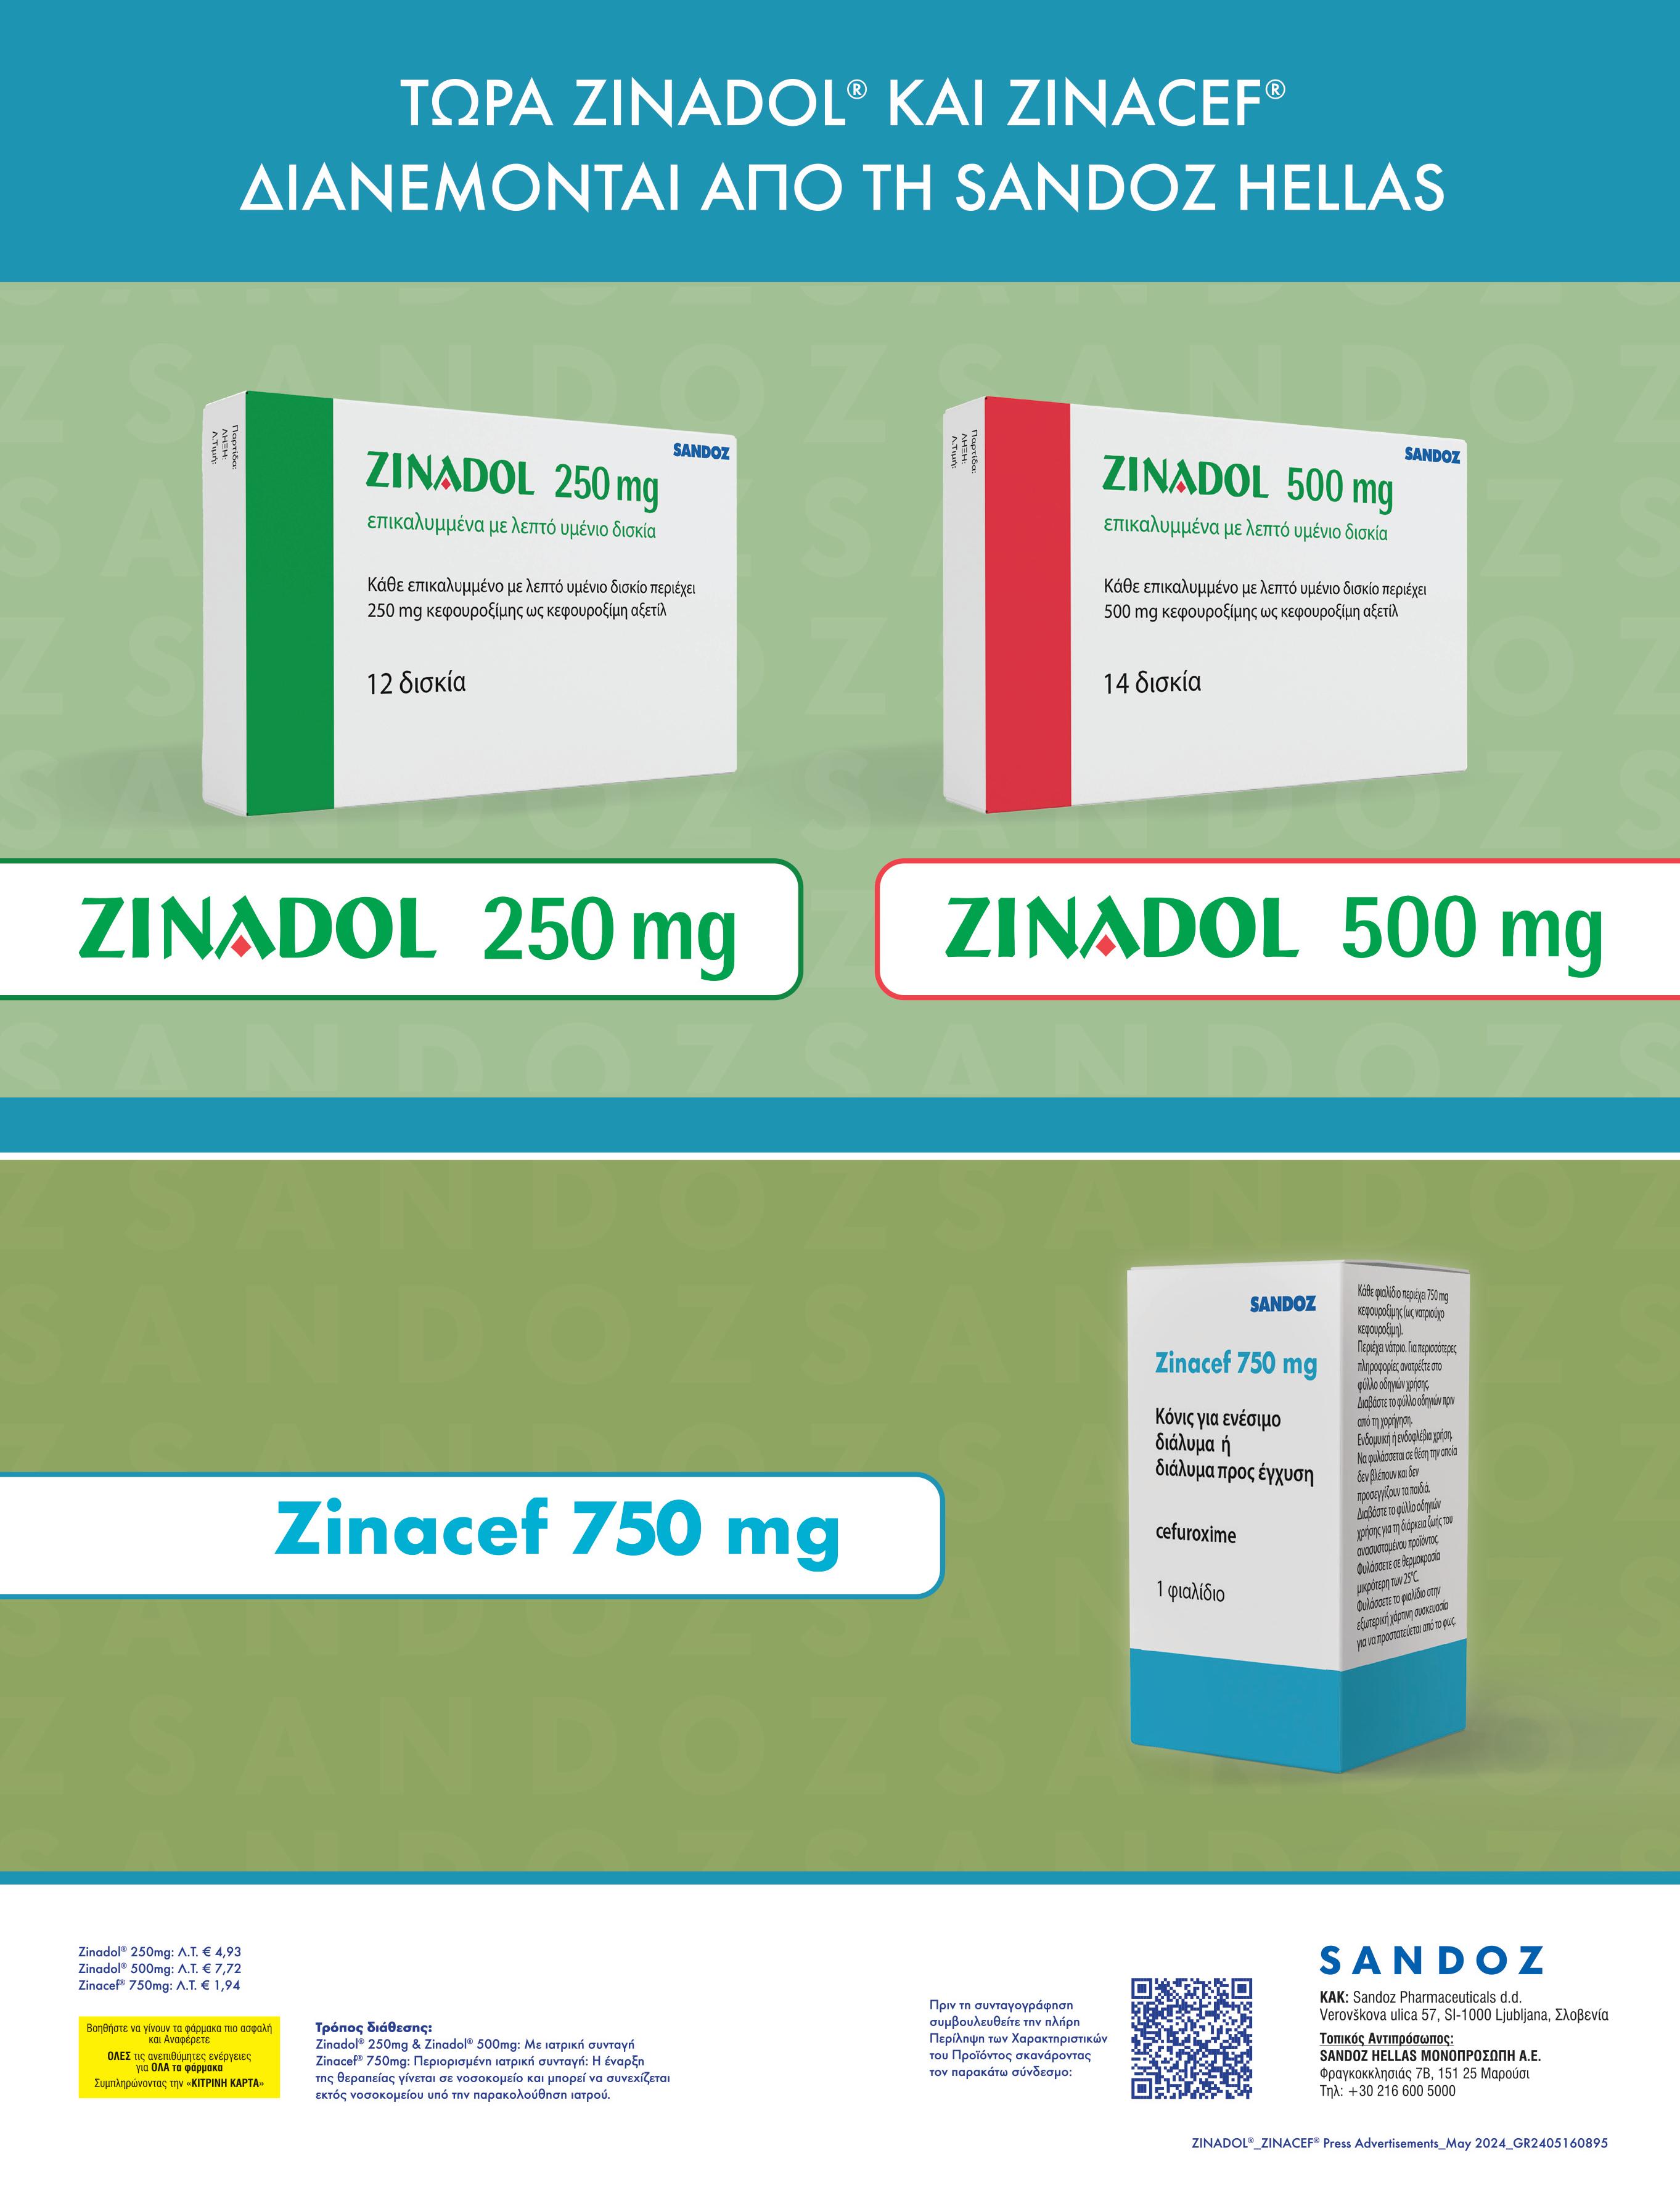

Candida (Candida albicans, Candida glabrata, Candida

(clotrimazole, econazole, fenticonazole, isoconazole, miconazole). δισκία

(itraconazole, fluconazole).

(clotrimazole, econazole, fenticonazole, isoconazole, miconazole).